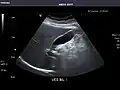

Spleen -

Spleen: Normal in size.